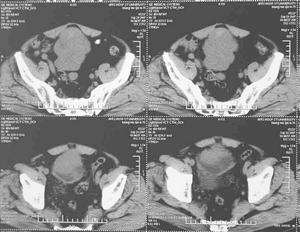

診斷:診斷較難。X線鋇造影檢查或內鏡檢查發現小腸潰瘍,如能排除其他疾病。應考慮本病。經口空腸黏膜活檢有時可獲有診斷價值的標本,但應注意避免引起腸穿孔。手術探查,術後腸切除標本活檢是診斷的可靠依據。

其他輔助檢查:X線鋇造影檢查或內鏡檢查發現小腸潰瘍,經口空腸黏膜活檢有時可獲有診斷價值的標本。